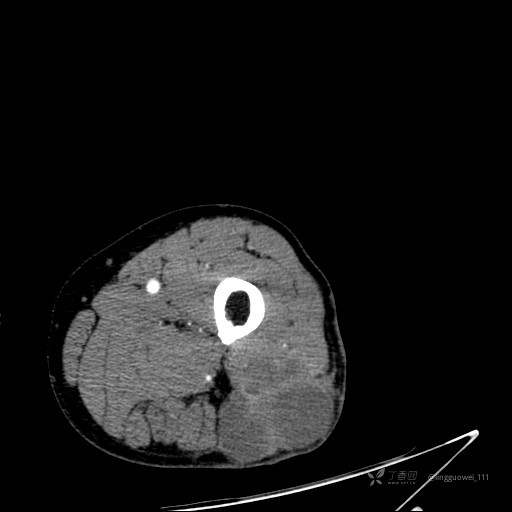

患者性别:男,85岁。发现大腿软组织肿块1年,增大3月,良性还是恶性?只有CT,能诊断正确吗?

增强动脉期